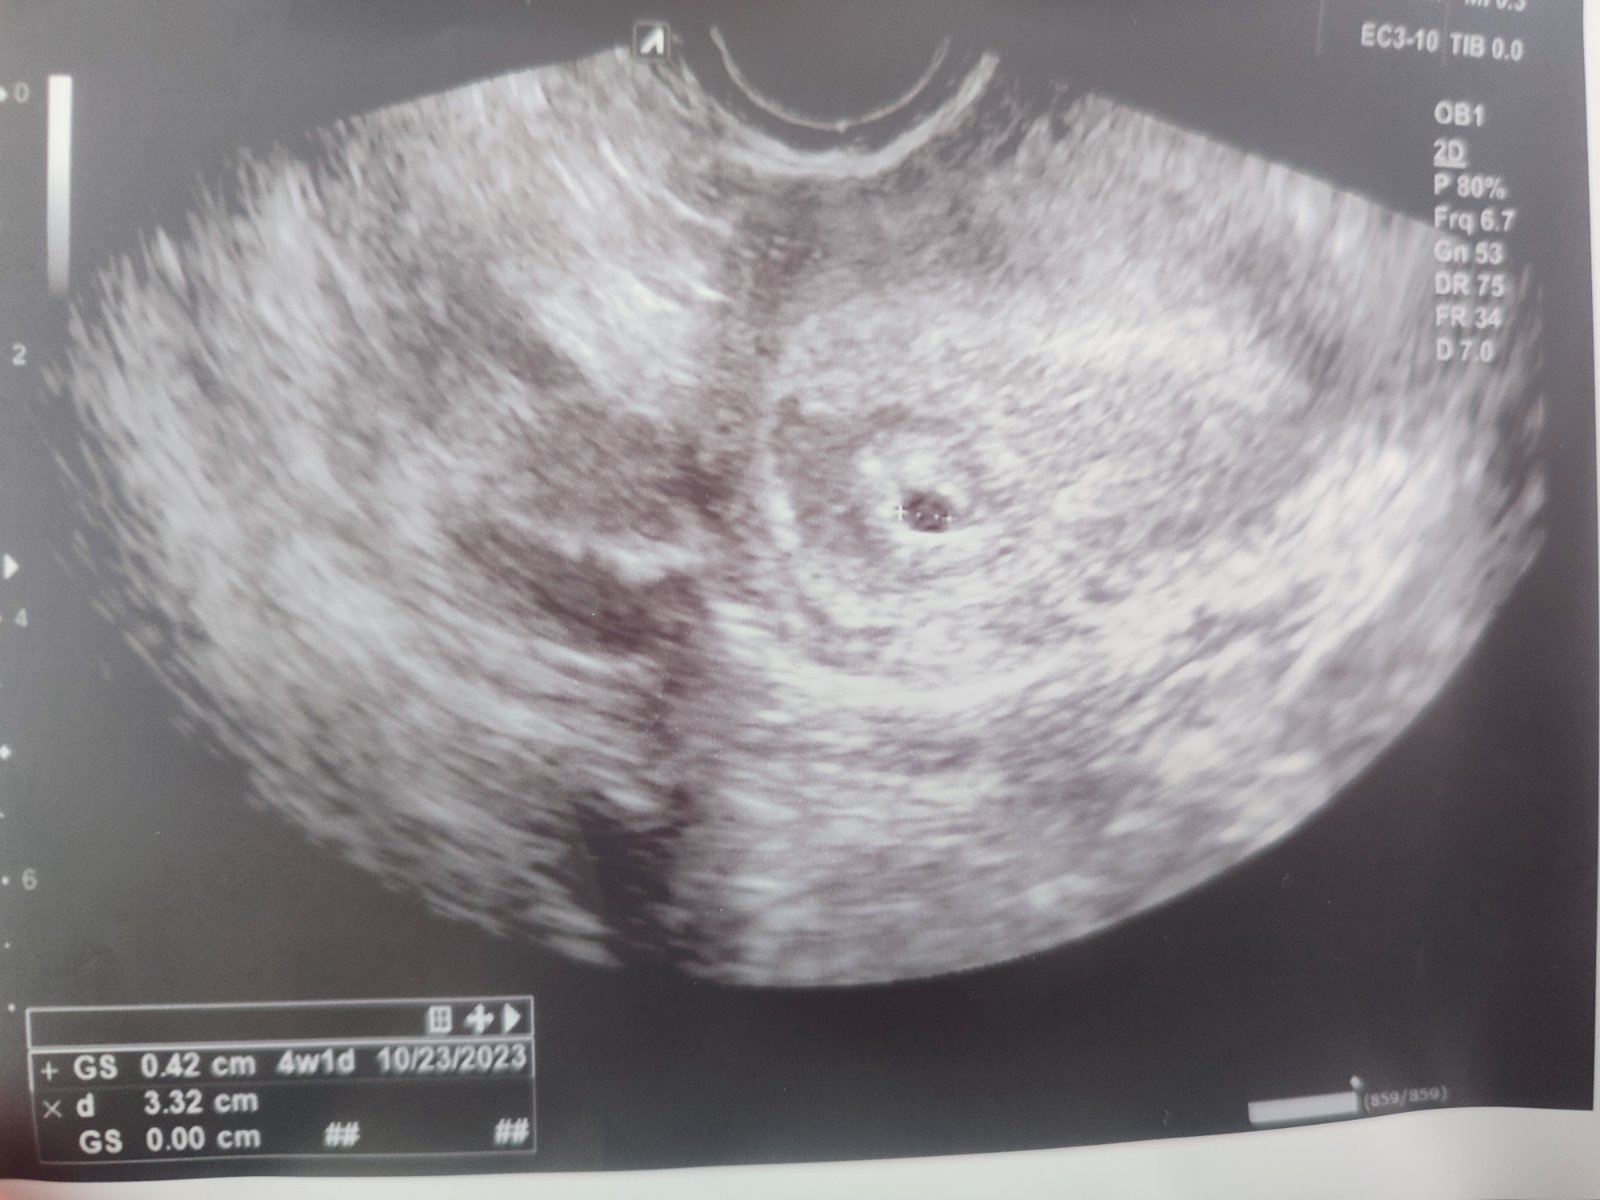

Na prvej kontrole som bola 14.2.2023 a doktor videl iba gestačný vak, ktorý veľkosťou zodpovedá 4. týždňu + 1 deň. Ja som však mala byť už v 5. týždni + 6 dní.